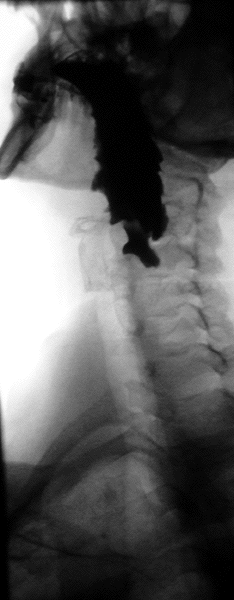

Normal barium swallow fluoroscopic image, showing the ingested barium sulfate being induced down the oesophagus by peristalsis. | |

Barium swallow

A barium swallow study is also known as a barium esophagram and needs little if any preparations for the study of the larynx, pharynx, and esophagus when studied alone.[11][12]

Amongst the uses of barium swallow are: persistent dysphagia and odynophagia despite negative esophagogastroduodenoscopy (OGDS) findings, failed OGDS, esophageal motility disorder, globus pharyngeus, assessment of tracheoesophageal fistula, and timed barium swallow to monitor the progress of esophageal achalasia therapy.[13] Barium sulfate suspension such as 100 ml or more of E-Z HD 200 to 250% concentration and Baritop 100% can be used. Water-soluble contrast agent such as Gastrografin (diatrizoate) and Conray (Iotalamic acid) is used instead of barium if oesophageal perforation is suspected. Low osmolar contrast medium with concentration of 300 mg/ml is used instead of gastrografin if there is risk of aspiration or there is tracheoesophageal fistula.[13]

A thick barium mixture is swallowed in supine position and fluoroscopic images of the swallowing process are made. Then several swallows of a thin barium mixture are taken and the passage is recorded by fluoroscopy and standard radiographs. The procedure is repeated several times with the examination table tilted at various angles. A total of 350–450 mL of barium is swallowed during the process.[14][15] Normally, 90% of ingested fluid should have passed into the stomach after 15 seconds.[16]

Right anterior oblique (RAO) view is to see the oesophagus clearly, away from overlapping spine.[13] AP (anterior-posterior) view is also done to visualise the gastroesophageal junction.[13] AP and lateral views are also done to visualise the hypopharynx during swallowing at a frame rate of 3–4 per second. Left posterior oblique (LPO) position is used to identify hernias, mucosal rings, and varices.[13]